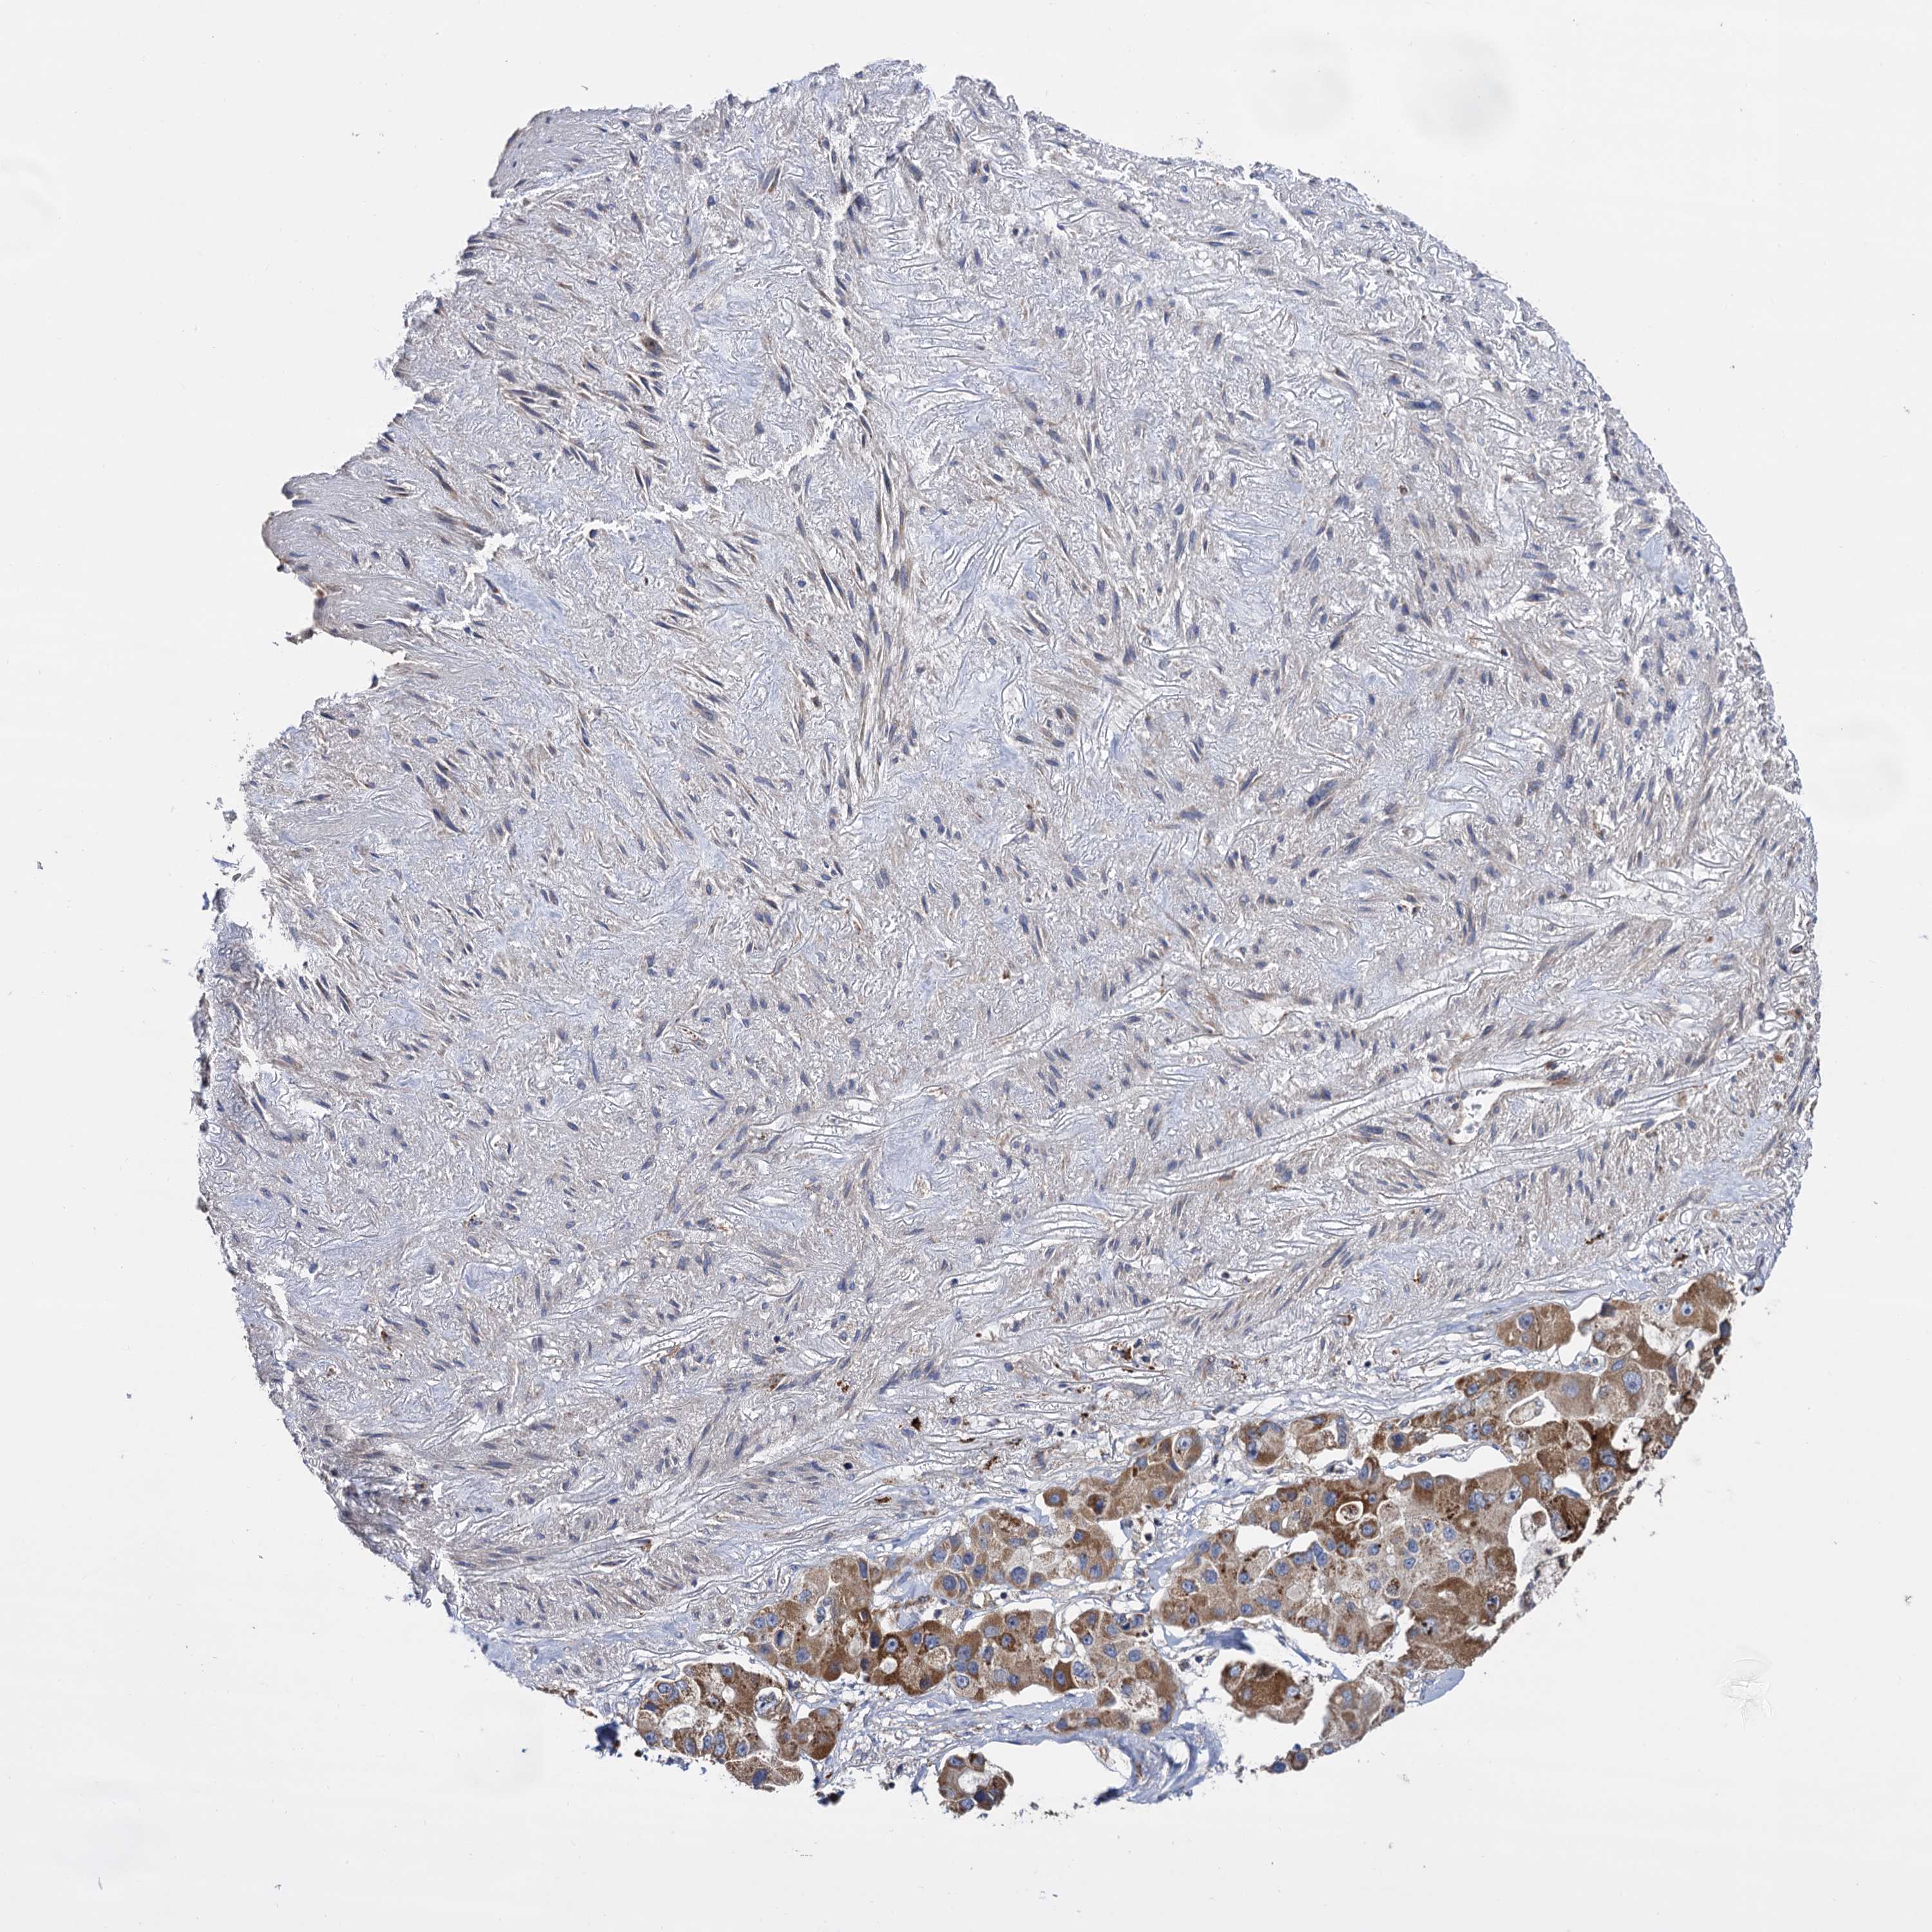

CANCER LUNG CANCER Show tissue menu

LUAD TCGA LUAD VALIDATION LUSC TCGA LUSC VALIDATION PROTEIN LUAD CPTAC PROTEIN LUSC CPTAC PROTEIN EXPRESSION